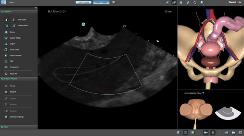

BASIC GYNAE TVS MODULE:

New Dedicated Separate Platform!

Physicians and Sonographers have the opportunity to practice varied common scenarios of routine or emergency Transvaginal Sonography.

True-to-life anatomies and pathologies include normal anatomical variations, early IUP, ectopic pregnancy, fibroids, ovarian malignancies, hydrosalpynx and more.

Step-by-step procedural tasks offer self learning of the standard positions to be demonstrated in TVS protocols.